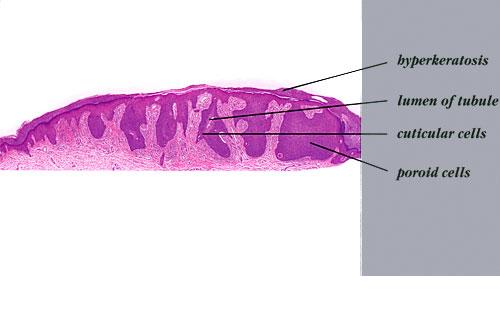

The term poroma refers to a group of rare cutaneous appendage tumors composed of cells (cuticular and poroid cells) similar to those of the acrosyringium. Poromas are traditionally subcategorized histopathologically based on their location in relation to the epidermis into three main variants; namely, hidroacanthoma simplex, eccrine poroma, and dermal duct tumor. Some authors add poroid hidradenoma to this group. There are also reports of “poromas” with differentiation toward the folliculosebaceous-apocrine unit.

Hidroacanthoma simplex shows sharply demarcated aggregations of cuboid to ovoid cells confined to the epidermis. Eccrine poroma reveals aggregations of uniform basaloid cells that radiate from the basal layer of the epidermis into the dermis . Dermal duct tumor consists of several sharply circumscribed, mainly dermal nodules composed of poroid and cuticular cells. Ductal structures are frequently observed. Poroid hidradenoma is characterized by intradermal, solid, and cystic aggregations of poroid cells.